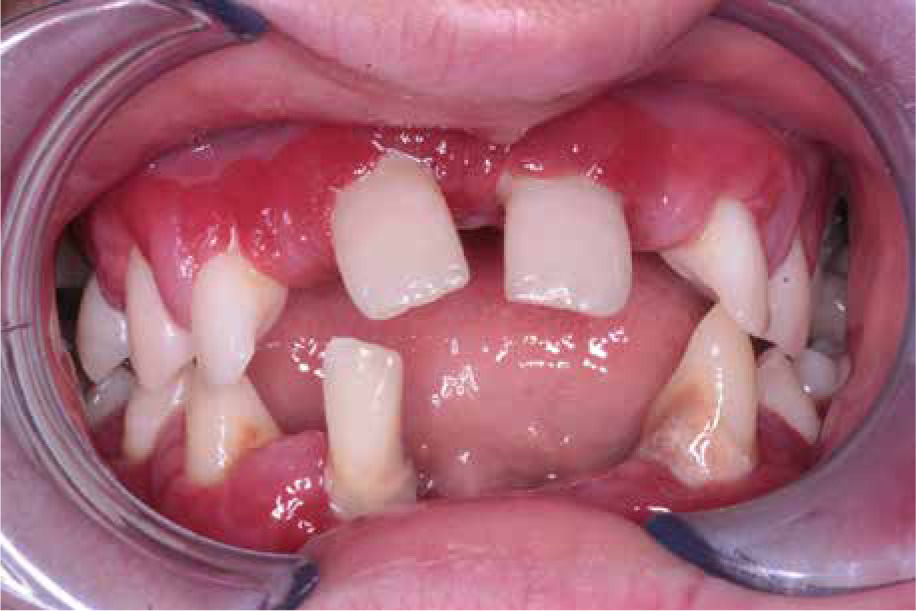

When he was 5 years of age the intraoral examination revealed incomplete primary dentition with five missing teeth, marginal gingivitis, interdental papilla hypertrophy, carious lesions in seven primary teeth, and one permanent tooth of various degrees of advancement for conservative treatment (Fig. 1). The patient was qualified for simultaneous dental treatment under general anesthesia. A panoramic radiograph picture was taken showing the advanced destruction of the alveolar bone in the maxilla and the alveolar part of the mandible. Three primary teeth were completely devoid of bone base. The roots of the lower incisors were only half of their normal length (Fig. 2). Under antibiotic protection (amoxicillin with clavulanic acid at a dose of 30 mg/kg), professional removal of dental plaque and conservative treatment of teeth extraction of four primary teeth with complicated caries and periodontitis were performed. The patient was provided with permanent dental care.

During follow-up visits symptoms of gingivitis and periodontitis were observed.

Every time oral hygiene instruction was provided and professional oral cavity hygiene and conservative treatment of cavities were performed under antibiotic prophylaxis. The patient was recommended to use topical chlorhexidine gel 2-3 times a day for 10 days and to rinse the mouth with a preparation containing octenidine twice a day for 10-14 days.